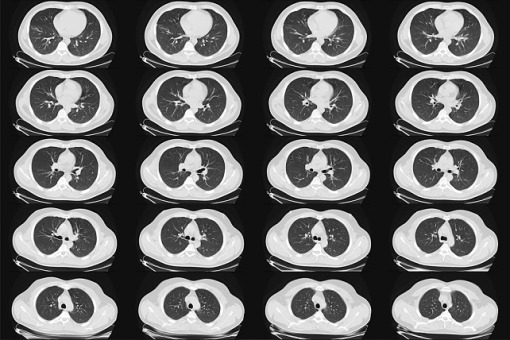

Choroby płuc – w tym przewlekła obturacyjna choroba płuc (POChP), rak płuca, astma, choroby śródmiąższowe – są w pierwszej piątce najczęstszych chorób cywilizacyjnych na świecie. W Polsce cierpią na nie miliony osób, a ich koszty społeczne są ogromne – alarmują eksperci.

Z danych wynika, że na świecie POChP jest trzecią przyczyną zgonów, a rak płuca pozostaje najgroźniejszym nowotworem, często określanym jako „cichy zabójca”, ponieważ jest pierwszą przyczyną zgonów wśród chorób nowotworowych. Szacuje się, że w Polsce na POChP chorują aż dwa miliony osób, choć formalnie zdiagnozowanych jest tylko 1,3 miliona. Oznacza to, że setki tysięcy pozostają bez rozpoznania i właściwej opieki. W naszym kraju choroby układu oddechowego nie tylko skracają życie, ale generują dotkliwe koszty społeczne i gospodarcze: obniżają wydajność pracy, obciążają rodziny pacjentów i pogłębiają nierówności społeczne, w tym różnice w oczekiwanej długości życia między ubogimi a zamożnymi.

– W Polsce mierzymy się z falą chorób płuc: POChP dotyka milionów osób, a skutki COVID-19 wciąż ujawniają się w postaci przewlekłych problemów oddechowych. To niewidzialna epidemia – objawy bywają bagatelizowane, ale konsekwencje są dramatyczne: od nagłych zaostrzeń wymagających hospitalizacji, po trwałe obniżenie jakości życia – podkreśliła dr Czajkowska-Malinowska.